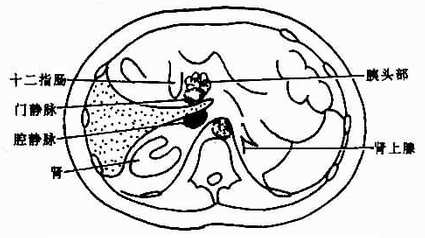

正常肝轮廓光滑,其形状及胸部结构依断面位置而不同。肝门区常有较多脂肪组织,呈不规则形或类似多角形低密度影。其中有肝动脉、门静脉和胆管进出。门静脉较大而居后,肝动脉位于其前内,胆管(主要是肝总管)位于其前外方。增强后门静脉较易识别,呈圆形高密度影,位于下腔静脉之前。CT上易于区分肝的各叶,即左呈、方叶、右叶和尾叶。左叶和方叶以圆韧带裂(又称纵裂)为界:方叶与右叶以右切迹和胆囊窝为界;横行的静脉韧带裂更明显。将左叶与尾叶分开;尾叶与右叶相连,突向内侧,位于下腔静脉的前方,易于识别。不同层面肝的解剖结构见图4-3-4。

图4-3-4 肝不同层面CT表现